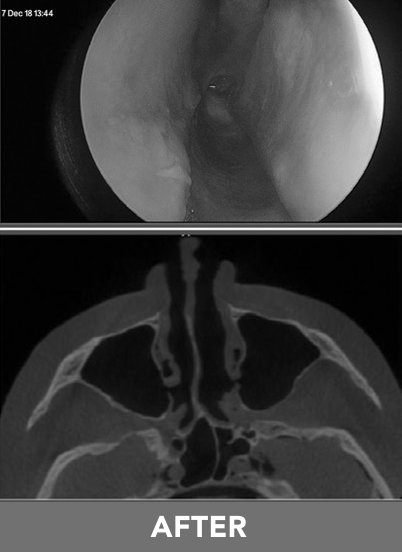

This is a minimally invasive procedure designed to relieve nasal airway obstruction (NAO). It works by gently opening the nasal passages with a small, inflatable balloon.

The RELIEVA TRACT® Nasal Balloon Dilation System is a state-of-the-art instrument designed to clear blockages and relieve symptoms of nasal airway obstruction. Below are the steps of what you can expect during your procedure: